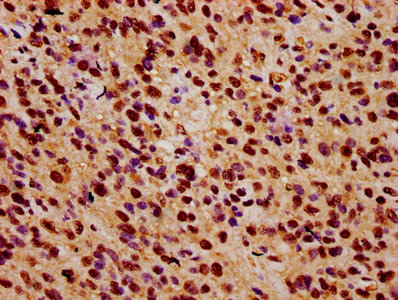

IHC image of CSB-PA026592LA01HU diluted at 1:500 and staining in paraffin-embedded human glioma performed on a Leica BondTM system. After dewaxing and hydration, antigen retrieval was mediated by high pressure in a citrate buffer (pH 6.0). Section was blocked with 10% normal goat serum 30min at RT. Then primary antibody (1% BSA) was incubated at 4°C overnight. The primary is detected by a biotinylated secondary antibody and visualized using an HRP conjugated SP system.